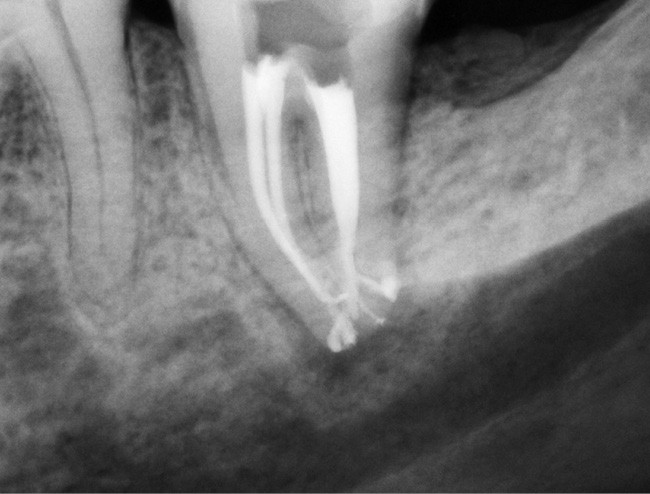

Endal, en 2011, montrait également, en utilisant le micro CT Scanner, l’insuffisance de nettoyage des isthmes inter-canalaires à nos techniques conventionnelles [19]. L’utilisation du laser Er:YAG devenait alors incontournable dans le nettoyage de ces isthmes et des zones non instrumentées (fig. 2 et 3).

Si l’étude de Peters [18] nous montre que l’instrumentation laisse 35 % du volume canalaire non instrumenté, Ricucci et Siqueira montrent que la préparation physico-chimique n’élimine que partiellement les tissus nécrotiques à l’entrée des canaux latéraux, des isthmes et des ramifications apicales, en laissant des tissus enflammés et infectés, en association avec des lésions apicales [29] (fig. 4 et 5).

Fig. 4 – Coupe d’une racine mésiale de molaire mandibulaire avec deux canaux traités. Coupe à 3 mm de l’apex, coloration Brown et Brenn, technique modifiée par Taylor. Ces images montrent un isthme étroit avec une infection bactérienne, ce qui prouve l’importance de désinfecter et d’inclure l’isthme dans les traitements conventionnels et dans les rétropréparations apicales en chirurgie endodontique.